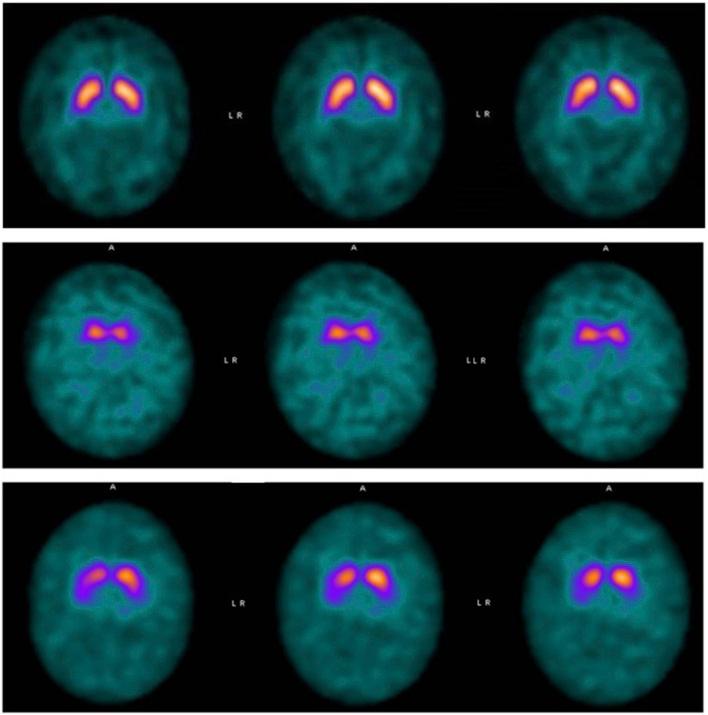

ATP13A2 is a gene localized on chromosome 1p36.13 and coding for a transmembrane protein found in the lysosomes and late endosomes, which is involved in many cellular metabolic activities. Pathogenetic variants of are associated with a wide range of neurodegenerative disorder including Kufor Rakeb syndrome (KRS), a rare autosomal recessive form of levodopa responsive juvenile onset parkinsonism (MxMD-), characterized by rapidly progressive muscular stiffness, bradykinesia, spasticity, pyramidal findings, dementia and supranuclear gaze palsy. The aim of this study is to provide detailed clinical descriptions of two siblings, carriers of novel biallelic variants. One of them showed KRS levodopa-responsive motor dystonic features at the age of 10 years preceded by moderate cognitive impairment, while the other only showed mild cognitive impairment at our last evaluation at 11 years of age. Additionally, we reviewed the previously published cases, focusing on early signs and symptoms, clinical evolution and response to therapy. To our knowledge, this is the only work that groups all reported KRS patients and compares their clinical and molecular features.

ATP13A2是一个位于1号染色体p36.13上的基因,编码一种存在于溶酶体和晚期内体中的跨膜蛋白,该蛋白参与许多细胞代谢活动。其致病变体与多种神经退行性疾病相关,包括库福尔-拉凯布综合征(KRS),这是一种罕见的常染色体隐性左旋多巴反应性少年型帕金森病(MxMD-),其特征为快速进展的肌肉僵硬、运动迟缓、痉挛、锥体束征、痴呆和核上性凝视麻痹。本研究的目的是提供两名携带新型双等位基因变体的兄弟姐妹的详细临床描述。其中一人在10岁时出现KRS左旋多巴反应性运动障碍特征,之前有中度认知障碍,而另一人在11岁的最后一次评估中仅表现出轻度认知障碍。此外,我们回顾了之前发表的病例,重点关注早期体征和症状、临床演变及治疗反应。据我们所知,这是唯一一项汇总所有报道的KRS患者并比较其临床和分子特征的研究。